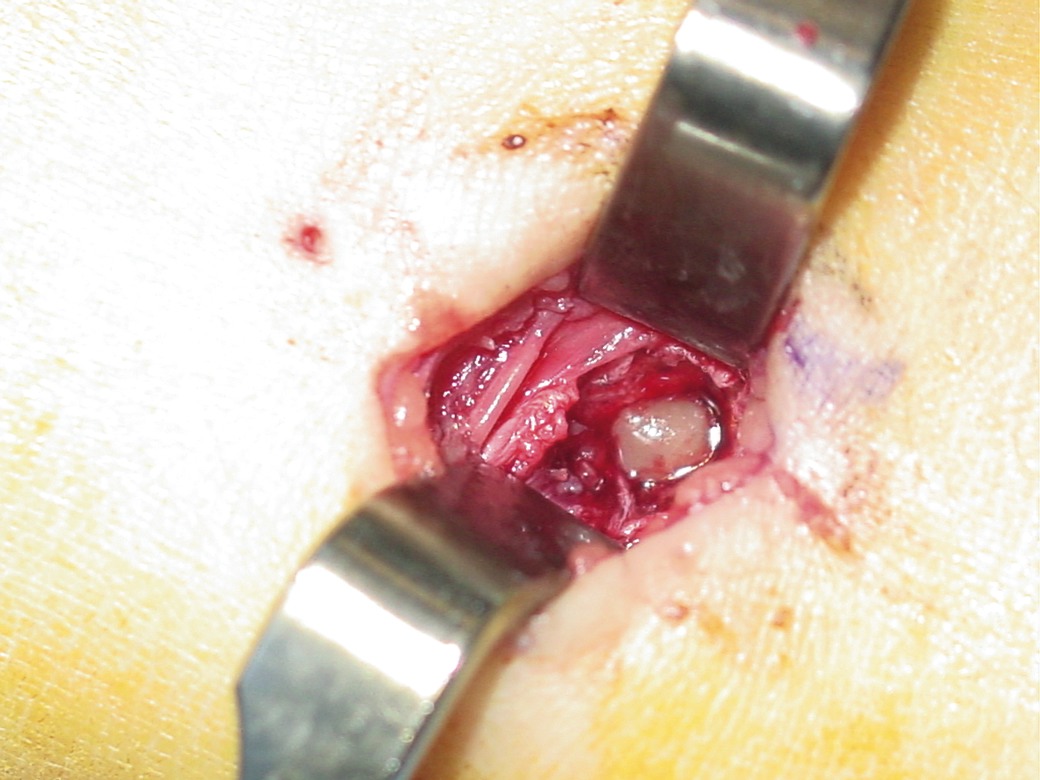

The treatment for AHO is usually antibiotic therapy and/or surgical intervention, which includes incision and drainage of abscesses, as well as debridement of infected, devitalized tissue and bone. One should begin empiric treatment by targeting gram-positive organisms. Researchers found that Staphylococcus aureus is the most common organism in 89 percent of these infections.1 Streptococcus pneumoniae, Group A Streptococcus and coagulase negative Staphylococcus are more age- and disease-specific.1 Researchers have found group B streptococci in greater frequency in neonates.1 One should ultimately tailor antibiotic therapy to target the culture results of soft tissue and bone specimens. Recent studies suggest using a sequential intravenous-oral antibiotic regimen.3 Again, it is important to differentiate between AHO and CRMO as CRMO does not respond to antibiotics but usually does respond to antiinflammatory medication.12

When it comes to CRMO, radiographic findings include osteolysis, expansion or periosteal reaction, sclerosis and onion skinning.19,31 Bone scans are ideal for identifying the multifocality of CRMO and one may subsequently use radiographs and CT scans to evaluate these focal areas.19 Clinical and radiologic differential diagnosis may include Ewing’s sarcoma, Langerhans cell histiocytosis (mainly tuberculosis), hematolymphoid malignancy and metastatic neuroblastoma.32 Along with the presenting factors and the presence of osteolytic lesions on X-rays, the clinician should consider the possibility of multiple inflammatory and neoplastic processes including hematogenous osteomyelitis, Brodie’s abscess, subacute osteomyelitis histiocytosis X, acute types of leukemia, rhabdomyosarcoma and metastatic neuroblastoma.19,33 Overall, CRMO is a great clinical and radiological mimic that merits the physician’s recognition.32 Biopsies are required to rule out an infectious bacterial osteomyelitis or tumoral process yet the histiopathic examinations in CRMO may not always show bacterial infestation.27 Researchers recommend open biopsies over percutaneous biopsies due to the high potential of contaminants.19 In a study of 17 cases of pediatric osteomyelitis by Coinde, et. al., histopathological exams showed only mild inflammatory, non-specific changes and cultures were negative.13 An article by Chow, et. al., also demonstrated poor correlations between histologic and clinical features.32 Van Howe reported a case of an 8-year-old girl who had toe pain for several weeks. Employing bone scan, he discovered multiple areas of other involved asymptomatic sites.19 The biopsy was negative and although the patient took no antibiotics or antiinflammatories, she recovered uneventfully. Since CRMO is essentially self-limiting, one would usually emphasize supportive treatment with antiinflammatory therapy and active rehabilitation after a period of prolonged rest.19 Studies have shown that children taking antibiotics to treat this condition did as well as those who did not. Duffy, et. al., showed some symptomatic benefit with intravenous bisphosphonates.31